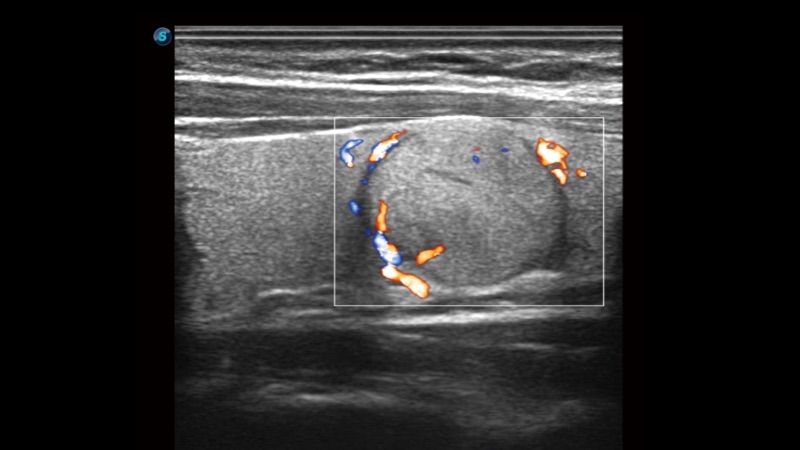

SR Flow高分辨率血流成像

高分辨率血流成像技术提高了对低速血流信号的检测能力。在提高空间分辨率的同时,也克服了血流外溢现象,为用户提供更加真实的血流动力学信息。

临床图像